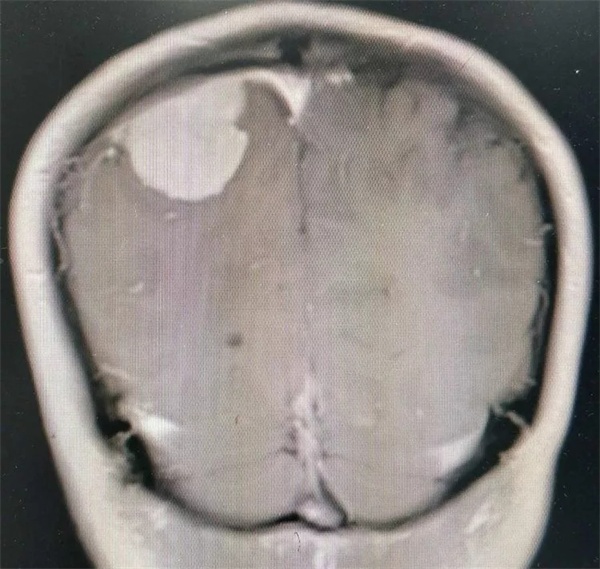

11月28日凌晨一点左右,朱某睡眠正酣,突发四肢抽搐,口吐白沫,双眼上翻,呼之不应,持续数分钟方才停止,睡在一旁的妻子目睹这一切,仿佛经历晴天霹雳,还以为丈夫“被鬼打了” 或“是中邪了”,一时间不知所措。待缓过神后还是拨打120,120把朱某送至捕鱼游戏 神经外科,头颅CT 检查提示右侧顶枕叶类圆形高密度占位,接诊医师姚勇、李世清考虑颅内占位所致继发性癫痫。